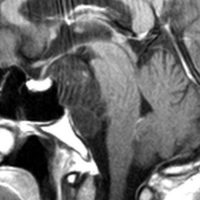

T2強調画像とFLAIR像です。FLAIRでは髄液より高信号となります。のう胞様の膨らみを有します。脊索腫と異なり,expanding mass と表現されます。

CISSとガドリニウム増強T1強調画像です。ガドリニウム増強されません。